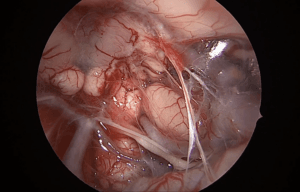

Reanimación facial con transposición del nervio maseterino

Análisis técnico de la anastomosis maseterino-facial para parálisis facial crónica post-resección de tumor. Se detallan las referencias anatómicas para la localización del n. maseterino y la rama cigomaticobucal, y la técnica de microsutura.